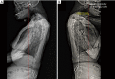

Rheumatoid arthritis (RA) is an autoimmune disease that affects the synovial tissue which lines joints and tendons. The craniocervical junction is made up exclusively of synovial joints and ligaments and especially vulnerable to the inflammatory process of RA. The chronic inflammation of RA leads to loss of ligamentous restriction and erosion of the bony structures and results in craniocervical instability (CCI). This is a case report of an 80-year-old woman who had been diagnosed with seropositive RA two decades ago presented with head dropping and losing balance while walking for several months. Radiographic images of the cervical spine showed RA-related features of instability in the form of atlantoaxial instability, cranial settling and subaxial subluxation. Since physical therapy and acupuncture previously failed to provide a substantial, long-lasting outcome, the patient sought chiropractic care for her condition. The chiropractic regimen consisted of upper thoracic spine mobilization/adjustment, electrical muscle stimulation of the cervical extensors, home exercises and neck bracing. She regained substantial neck muscle strength, gaze angle and walking balance following a 4-month chiropractic treatment, although cervical kyphosis persisted. The current study aims to provide basic knowledge of CCI associated with RA and ability to modify a treatment program to accommodate the needs of patients with coexisting red flags.